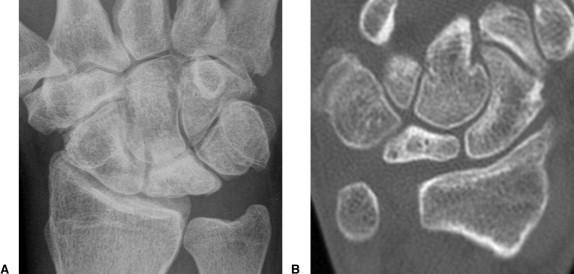

Lunate 의 sclerosis가 발견되면 Stage II 이며 Joint leveling 이 핵심입니다. ulna 변위가 중립 혹은 양성인 경우에는 radial wedge osteotomy나 그 외의 치료를 시행해 볼 수 있습니다.

Stage III 부터는 주상골도 영향을 받기 시작하며 회전을 하거나(IIIA, cortical ring 관찰가능), carpal height 가 줄어드는 것을 확인할 수 있습니다. (IIIB), IIIA 까지는 II와 치료를 거의 동일하게 하지만, IIIB 부터는 Proximal row carpectomy 나 STT, SC fusion 등을 시행해 볼 수 있습니다.

단계별로 보면 다음과 같습니다.